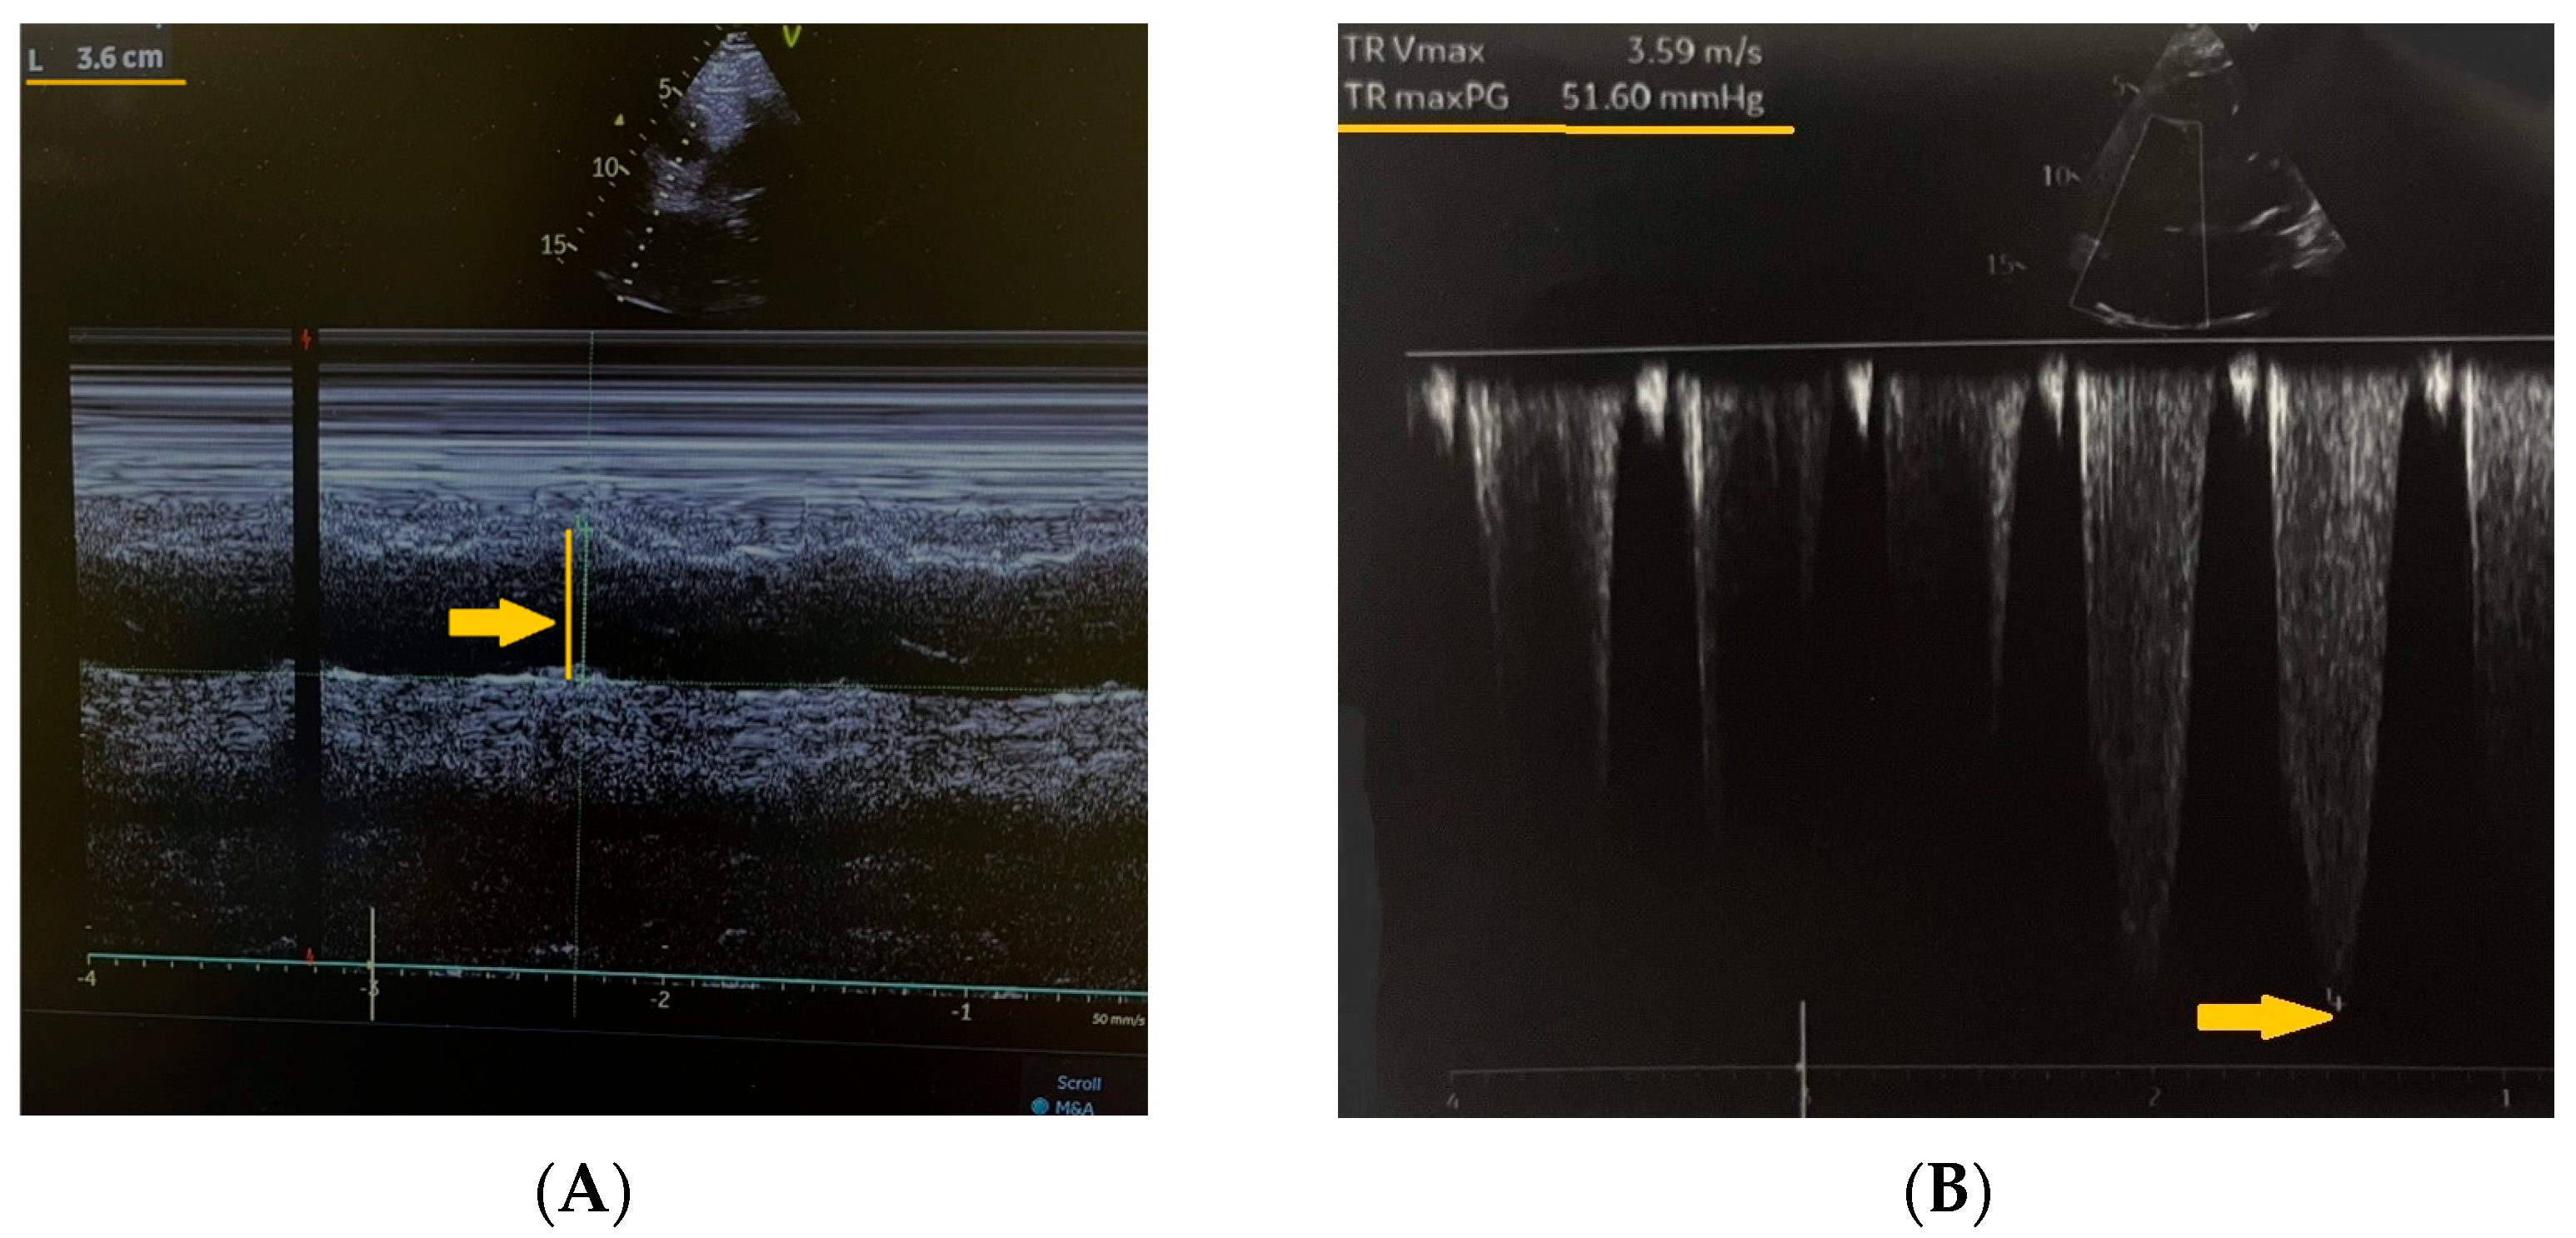

The estimated systolic pulmonary artery pressure was approximately 70 mmHg (normal resting value: <35 mmHg). Ultrasound examination of the right calf revealed a thrombus in the popliteal vein as documented in the surgical consultation records (Figure 3).

Figure 3. Ultrasound examination of the right calf revealing a thrombus in the popliteal vein (yellow arrow).